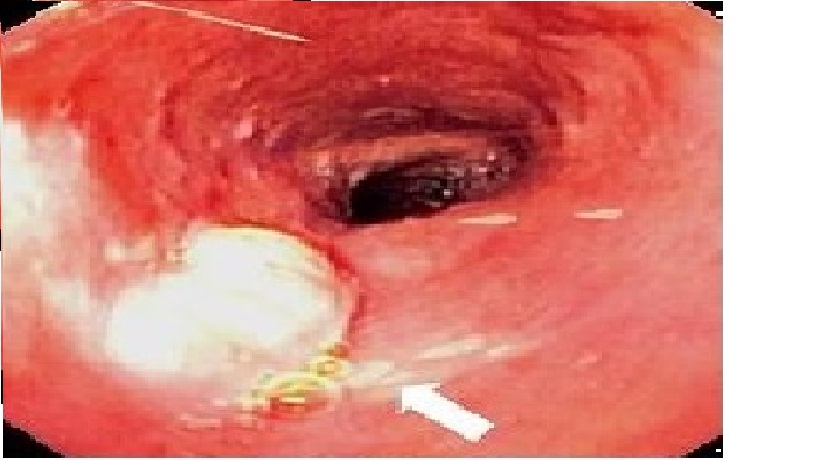

Nowy system do endoskopii balonowej (ang. Balloon Guided Endoscopy - BGE) (NaviAidTM BGE; Smart Medical Systems Ltd.) umożliwia przeprowadzanie enteroskopii przy użyciu niniejszej technologii, jak np. enteroskopii dwu-balonowej (ang. double balloon enteroscopy - DBE). Jednakże w odróżnieniu od metody DBA, mogą być używane endoskopy standardowe.

Celem bieżącego badania było przetestowanie skuteczności i bezpieczeństwa nowego urządzenia przy użyciu różnych endoskopów (HD plus, współogniskowego, standardowego) wyregulowanego do wskazań enteroskopii.